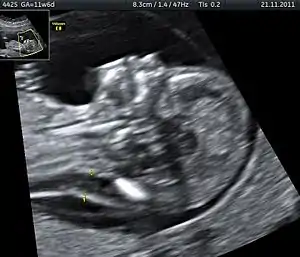

| تشخیص احتمال مردهزایی معمولاً با استفاده از سونوگرافی انجام می گیرد | |